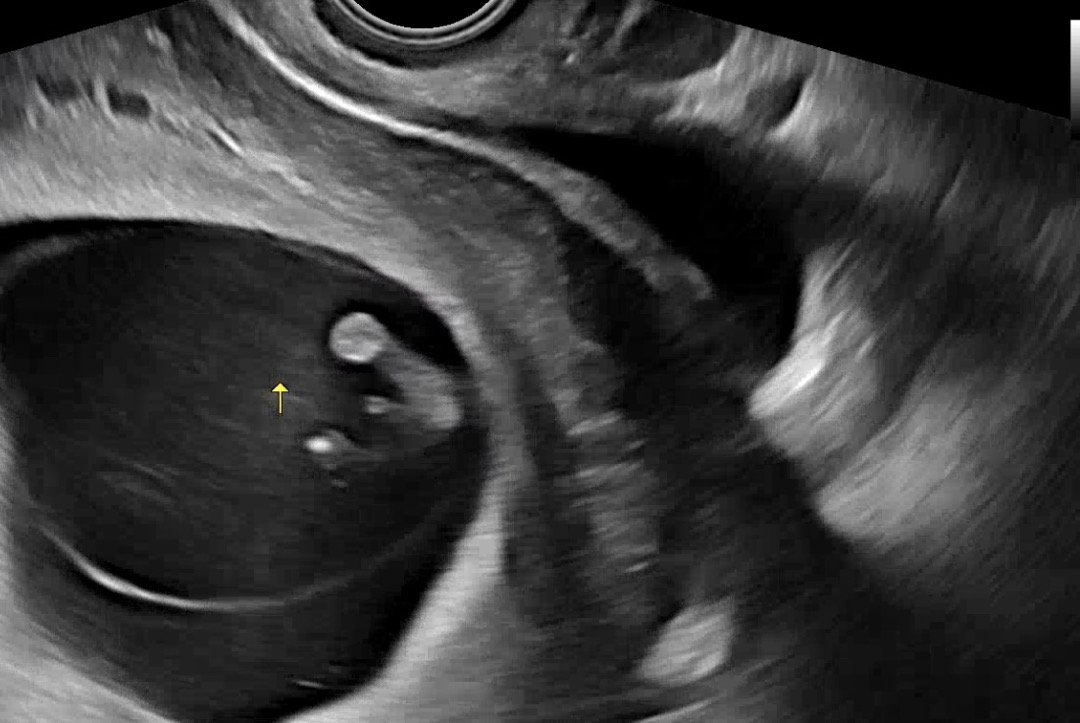

10주2일차 초음파 성별

10주2일차에 찍은 초음파인데.. 아직 성별 알기에 빠르죠..? 존재감이 뚜렷해서 혹시나 아들인가 해서용,,🌶️🌶️